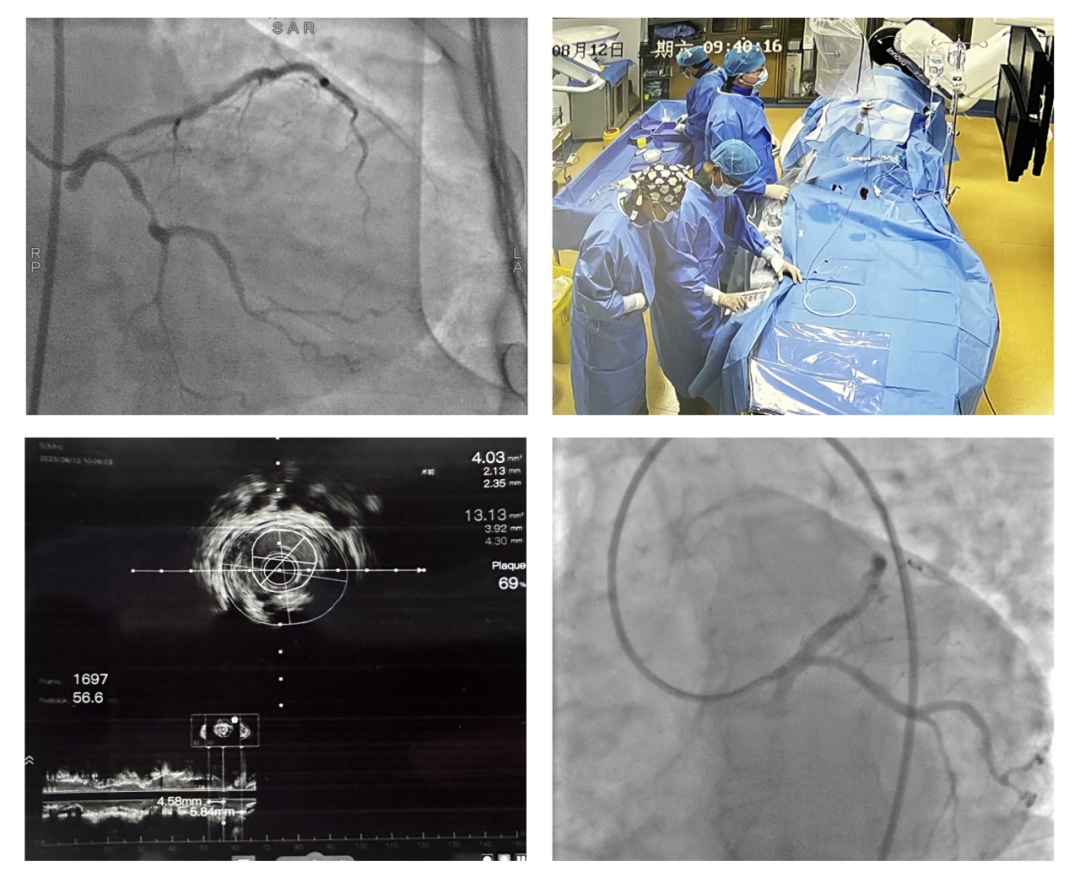

12日早上,华山医院心内科团队和丘北县人民医院心内科共同开展冠脉手术。手术由朱志栋医生主刀,王逸明医生和丘北县人民医院心内科陈伟明医生辅助。朱医生师从于华山医院心内科施海明教授、罗心平教授以及葛雷教授,主攻冠心病的介入治疗,擅长攻克复杂冠脉病变,高危病变以及慢性全闭塞病变(CTO)等。此刻,他们面对的是曾经被称为“介入禁忌”的主干病变,团队沉着应战、密切配合,在血管内超声辅助下有条不紊地完成了两例手术,同时实现了丘北县人民医院冠脉介入中主干支架和血管内超声两项“0”的突破。“五年前,我去了华山医院心内科学习心脏介入技术,并回到家乡开展了相关工作,为的是造福一方人民。”陈伟明医生在术后说。

冠脉手术团队通过血管内

超声辅助实施左主干支架植入